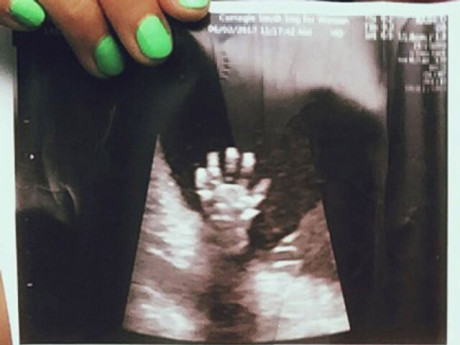

Trên thực tế có vô vàn khoảnh khắc dễ thương của em bé trong bụng mẹ được các gia đình chia sẻ đem đến cảm xúc vui vẻ và ấm áp cho người xem:

Có vẻ như mút ngón tay là trò chơi yêu thích của thai nhi bé bỏng này.